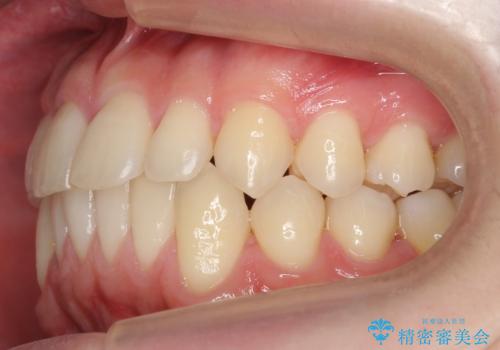

- 前歯の並びをきにして来院。

歯を抜かずに、やすりがけすることでスペースを獲得し、前歯をしっかり下げました。

また、インビザラインに先駆けて、右下はワイヤーによる部分矯正を行い、犬歯をしっかり後ろに下げました。

下げる時に、矯正用ミニスクリューを使用しています。